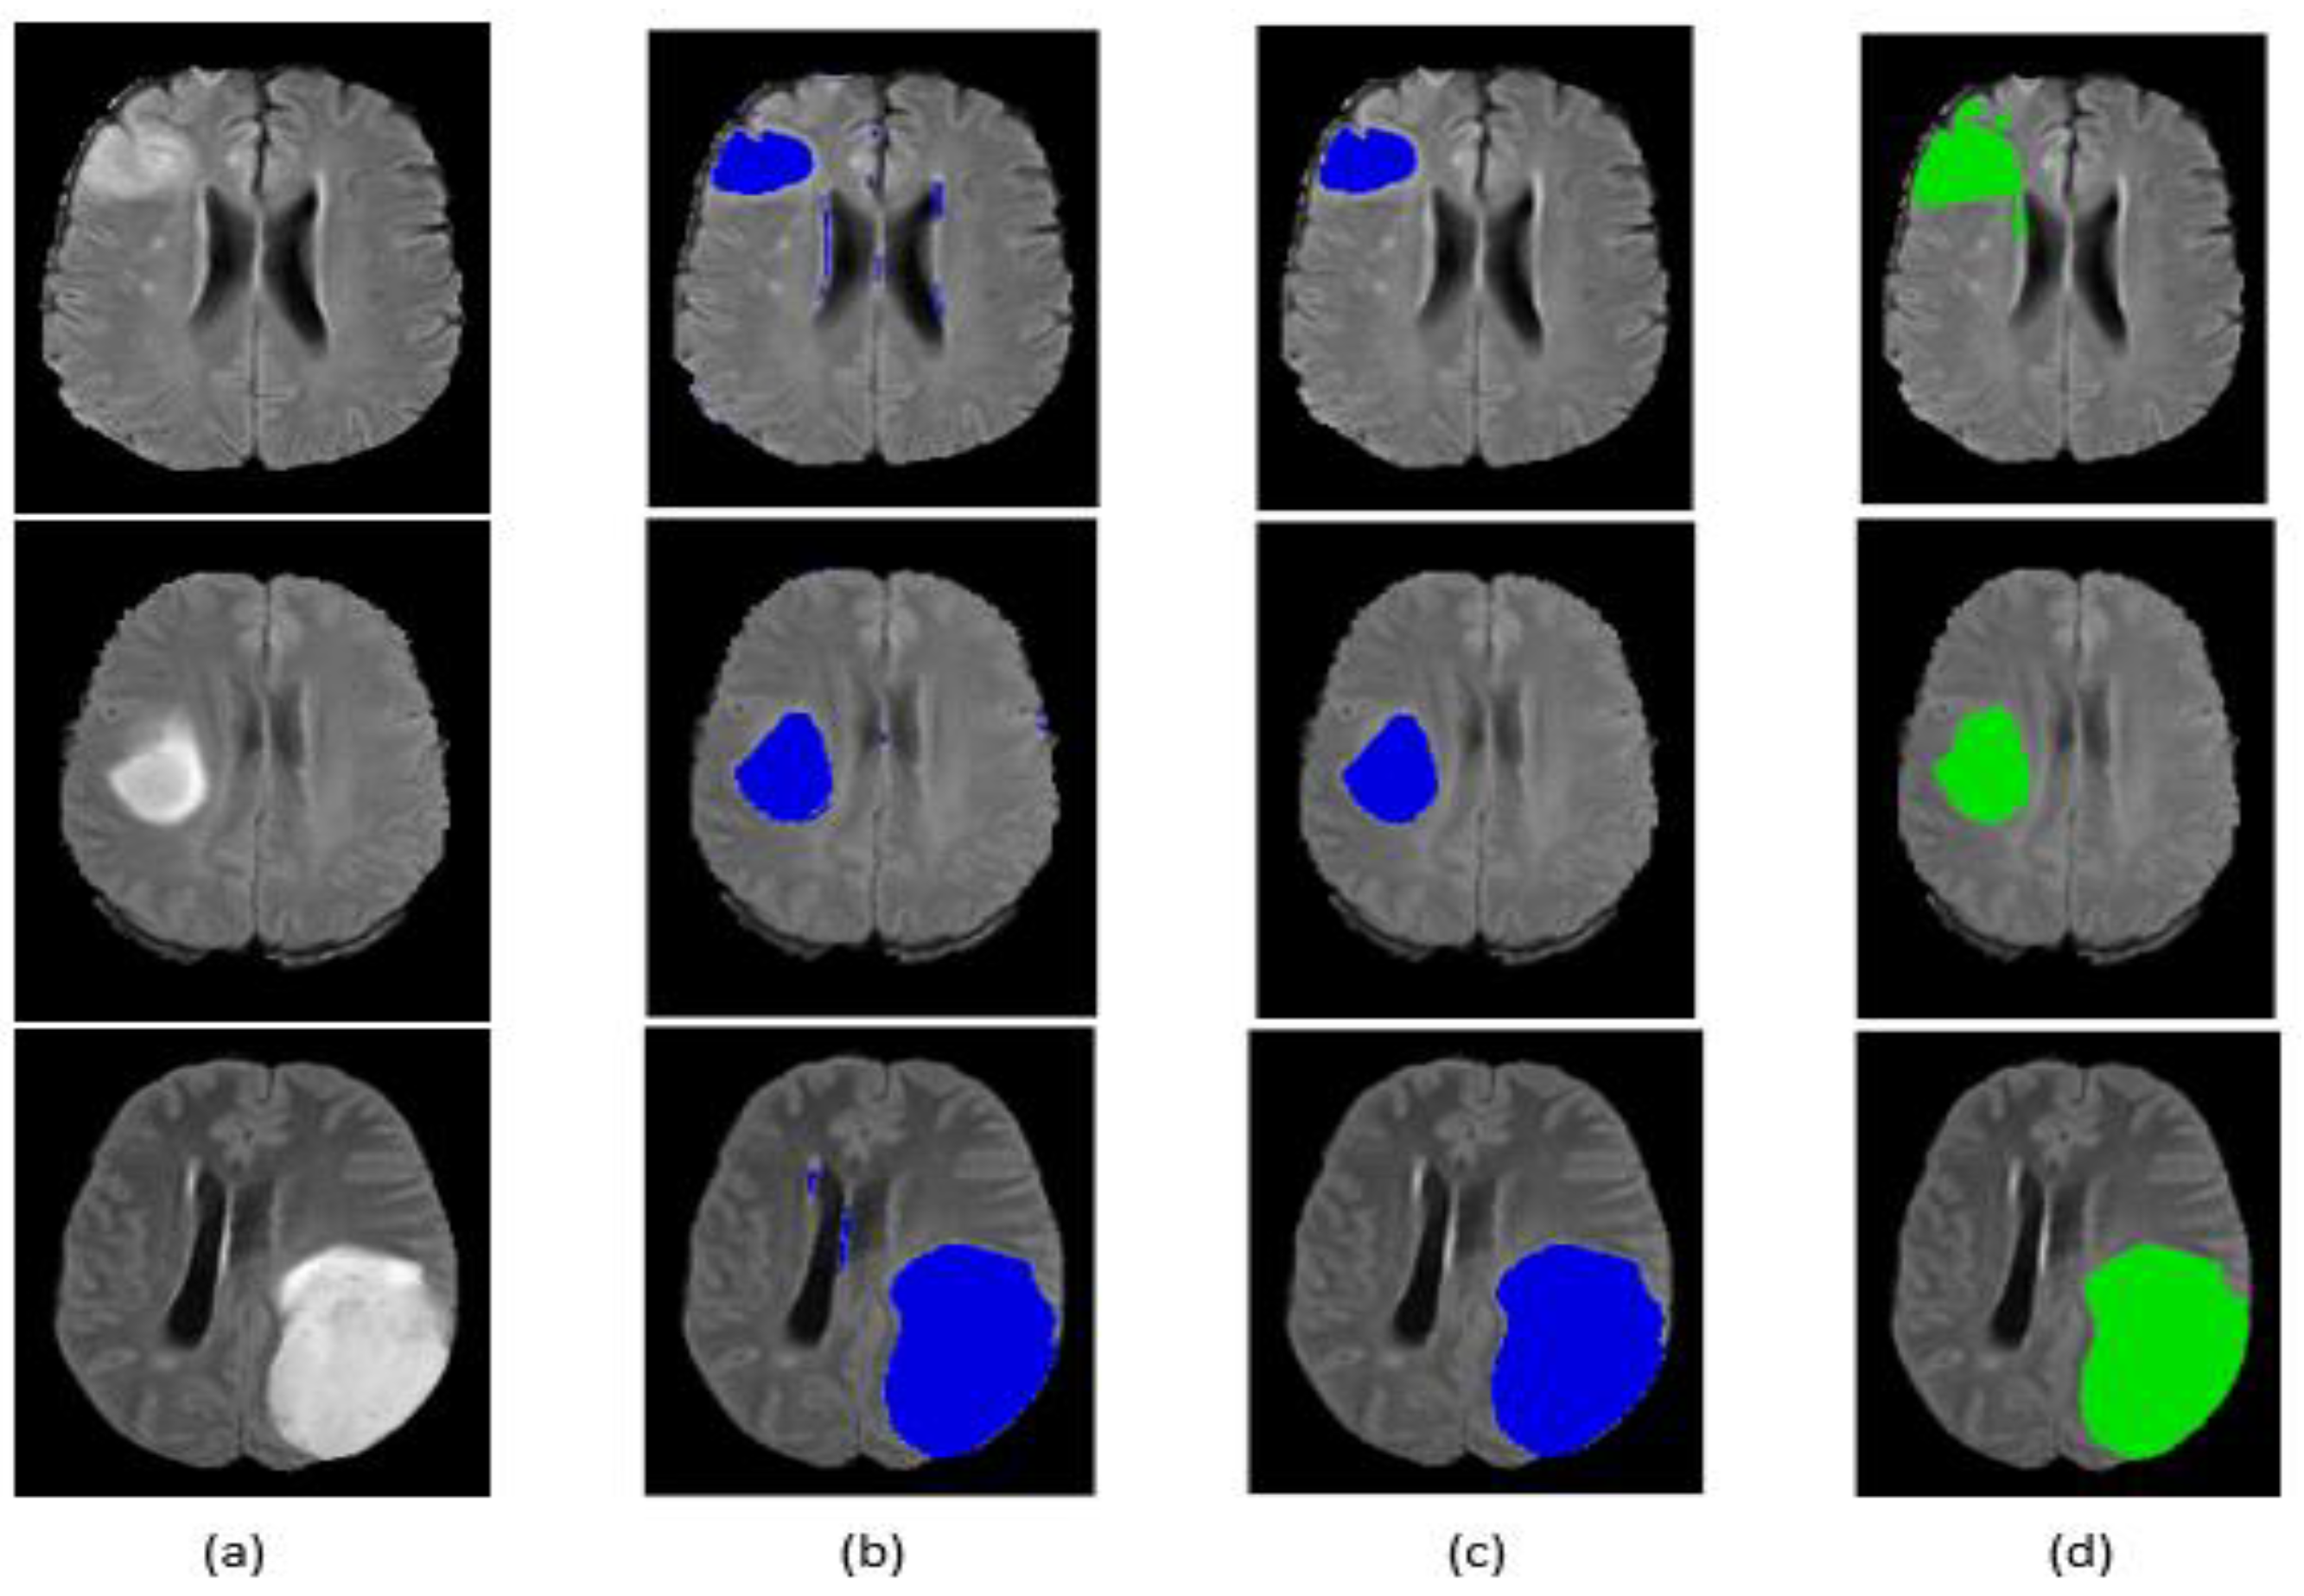

Qualitative segmentation results are presented in Figure 9 and Figure 10 for the BraTS 2017 dataset. The figures also indicate that our network is capable of accurately segmenting complete tumor regions. Our approach was tested on the FLAIR modalities for MRI images outside the BraTS 2017 dataset, and it provided good results, which guarantees the performance and power of the proposed method.

Figure 10.

Segmentation result of our method on some BraTS 2017 LGG images: (a) original image, (b) segmentation before post-processing, (c) segmentation after post-processing, (d) ground truth.